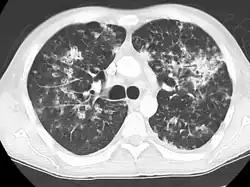

A case of miliary tuberculosis in an 82-year-old woman:

-

X-ray, 13 days after onset, showing bilateral interstitial infiltrates -

CT, 16 days after onset, showing extensive pulmonary parenchymal involvement consisting of irregular septal thickenings with ground-glass areas and centrilobular nodules with a peri-lymphatic distribution -

X-ray, 22 days after onset, showing extensive bilateral reticulo-nodular infiltrates -